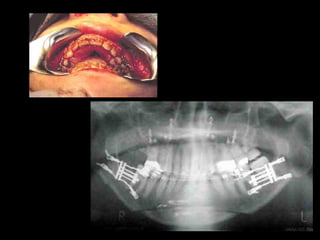

Obtenido de casos de internet

Mi casuística

24 horas de postoperatorio

24 horas depostoperatorio